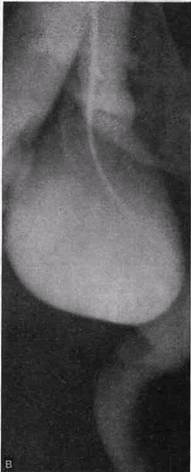

Рис. 26. Аневризматические подклапанные расширения большой подкожной вены вблизи ее устья (а, б, в) (ретроградное контрастирование).

оси сосуда, тогда и возникает равномерное аневризматическое расширение вены.

Наиболее часто значительные локальные расширения большой подкожной вены встречаются в ее проксимальном отделе. Вена расширяется ниже остиального клапана. Такие расширения большой подкожной вены нередко ошибочно диагностируют как бедренную грыжу (рис. 26, а—в). Поводом для диагностической ошибки Служат: 1).одинаковая локализация; 2) спадение в положении лежа и напряжение в положении стоя:

Аневризматические расширения большой подкожной вены в ее проксимальном отделе обычно наблюдаются у больных во II стадии болезни, когда подкожные вены значительно расширены. Поэтому само наличие варикозной болезни должно служить поводом для дифференциальной диагностики, так как иногда и у больных с варикозной болезнью встречаются бедренные грыжи.

Аневризматические расширения вен наблюдаются и в пределах нижней трети бедра, порой они также бывают значительных размеров. Диагностика таких расширений не вызывает затруднений (рис. 27). Обычно термин «аневризма» применяется в связи с локальными расширениями артерий или вен, но под действием артериального кровотока.

| Рис. 27. Аневризматическое расширение большой подкожной вены (контрастирование посредством пункции аневризмы). |